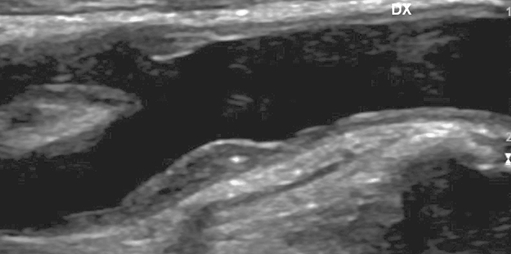

• Триплексное сканирование брахиоцефальных артерий

• атеросклероз внечерепных отделов магистральных артерий головы со стенозом в области каротидной бифуркации слева до 54%.